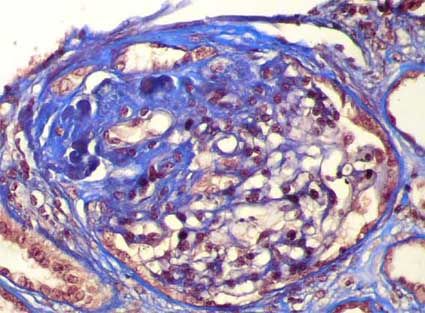

1. Microscopio óptico

1. En segmentos escleróticos: Colapso de asas capilares

1. Glomérulo con esclerosis en la mitad superior teñida en azul, la mitad inferior presenta una arquitectura conservada

2. Aumento de la matriz con depositos de proteínas plasmáticas a lo largo de la pared capilar (hialinosis) que pueden ocluir las luces capilares